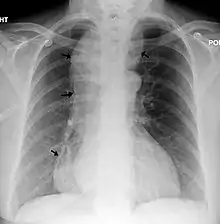

يشخص المريض بعد ظهور الأعراض المذكورة باستخدام التقنيات الإشاعة الحديثة مثل الأشعة السينية التي قد تظهر فقاعات هوائية داخل المريء وأيضا يمكن أستخدام تقنية الحقن لمادة الباريوم لتظهر لنا التضيق في الصمام السفلي للمري الناتج عن تشنج هذا الصمام، فيظهر توسع في المريء الصدري الناتج من ارتجاع السوائل والمواد الصلبة للمريء ويظهر أيضا علامة منقار الطائر، نظرا لتضيق الصمام من الأسفل